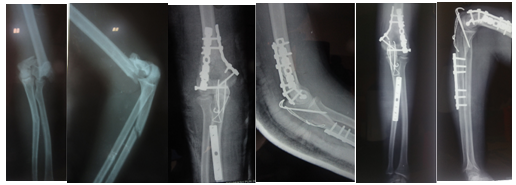

A 24-year-old teacher was injured in a high-velocity motor-vehicle accident. He sustained an ipsilateral intercondylar distal humerus fracture (AO 33 C1) and a Monteggia fracture-dislocation (Bado type II) in the left forearm (Figure 1), accompanied by an incomplete radial nerve palsy. On evaluation, head and other internal injuries were rule out. There were no other long bone fractures. The upper extremity injuries were treated two days after admission to orthopedic ward.

Figure 1 Pre, Post operative & 3 months follow up

a. Pre op b. Post C. 3 months follow-up

The Monteggia lesion was reduced first by plating the ulna fracture with seven hole, 3.5 mm dynamic compression plate. Closed reduction of radial head was achieved. The distal humerus was approached with extended posterior approach with Chevron osteotomy. Two 3.5 mm reconstruction plate was used for the humeral fracture and one 4.0 mm cannulated screw for intercondylar extension. The two plates were oriented at 900 to each other with the medial plate lying medial surface of the humerus and the lateral plate lying posterior 900 to this. The radial nerve was explore as there was nerve palsy. Per operatively, the radial nerve was entrapped within the proximal segment of the humerus. After fixation of chevron osteotomy with K-wires and tension band wiring, the ulnar nerve was transposed anterior to the medial epicondyle of the humerus. Post operatively, a long arm posterior slab was applied. The elbow was immobilized with splint for 12 days. Suture was removed and active range of motion exercises were begun after removal (Figure 1).

At 9 months follow up, the patient did not complain of any symptoms of radial nerve palsy. The radiographs demonstrated bony union of both distal humerus and ulna with correct position of the radial head (Figure 2). The patient had full extension, flexion to 135°, supination to 90° and pronation to 90°. The final result was excellent according to the Broberg and Morrey scale.